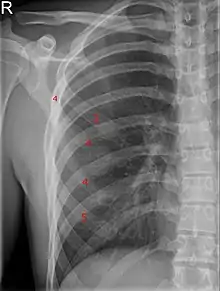

Bifid rib at the right side seen on chest radiograph. The fourth rib splits in two towards the sternal end.

A bifid rib is a congenital abnormality of the rib cage and associated muscles and nerves which occurs in about 1.2% of humans. Bifid ribs occur in up to 8.4% of Samoans.[1] The sternal end of the rib is cleaved into two. It is usually unilateral.[2]